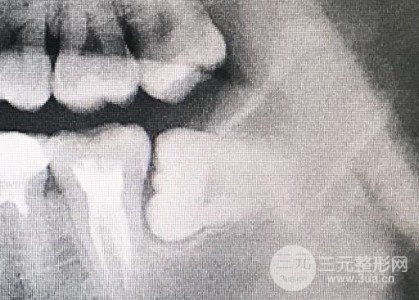

不同的智齿差别太大了。如果容易的话,打一针麻药几分钟后拔。回去冰敷半天,不会太疼,也不会肿。第二天,活蹦乱跳,甚至不用缝针。以前拍了片子,我有个比较大的智齿,阻生,她当时没有准备给我做,说这很复杂,还需要一段时间,而且有可能会伤害面部神经。我很害怕,就拖着。期间发炎两次,用甲硝唑克制。不过,这么老也不是个事。而且,今年牙齿的充血明X越来越严重。我早晚会担心出事,所以经过很多次的心理建设,我下定决心要消灭。选择了当地的珠海口腔医院,正好赶上疫情。医院的医生头一次没拔,说是担心疫情期间气溶胶,所以拔那个要切开拔的是不可能的。更多医生价格、预约、优惠等信息,点击在线免费咨询~

过了几个月以后,我可以直接去拔智齿了,以为和原来一样简单易行,不痛不肿。所以犯了轻敌的错误。先打麻药,再拔左上,一分钟后还是简单的,然后进入正题,右下阻生智齿。用布遮住脸,但只漏嘴,所以看不见,都是凭感觉。打麻药不疼,但我能感觉到医生用手术刀割破了我的牙龈。等了一个世纪后,医生说:“好了,缝合。”。在网上看帖子之前,我通常见到的是缝一下,但少数人会多一两下,但医生就像在我嘴里做百家布,一针接一针,似乎有四针或五针。它被拆成了四块。